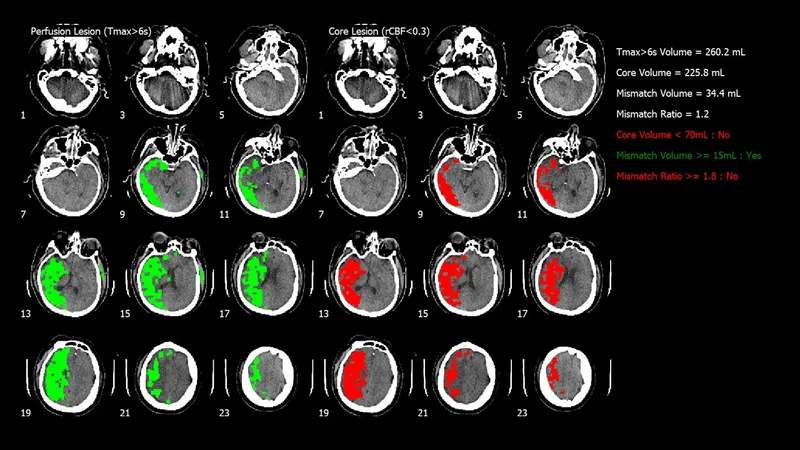

CTやMRIの脳血流画像から、脳血流パラメーターを自動計測、各種脳画像マップを作成して、診断に必要な情報を提供します。

MRI/CT装置などの外部連携機器から送信されたMRI拡散強調画像、MRIまたはCT灌流画像を受信し、全自動で診断に役立つ情報を定量的・視覚的に提供します。 ① 血流情報を基に、特定領域の容積を自動計測します。 ② 容積および各種定量値(CBV,CBFなど)を計測します。 ③ 様々な脳灌流解析マップを作成し、視覚的な状況把握を可能にします。 ④ 解析結果は、院内のPACS上で閲覧できます。